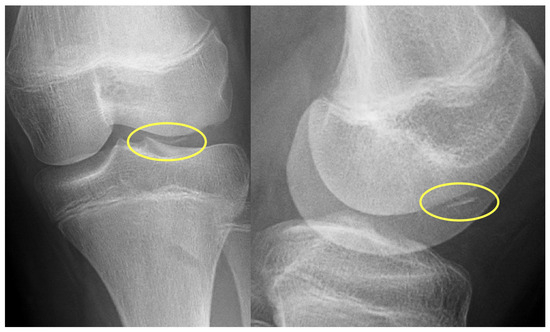

First patient: A nine-year-old girl injured her knee during a careless step, resulting in a sprain. The left knee was slightly swollen and the patient complained about pain, but other pathologies could not be identified with the physical examination. Therefore, an X-ray was requested. Results revealed an approximately 8 mm large broken piece of the femur’s lateral condyle, positioned at the border of the lateral recess (Figure 1).

Preoperative X-ray showing the osteochondral fragment (yellow circle) of the lateral condyle of the femur.

Second patient: A fifteen-year-old boy was admitted after he suffered a fall. The patient complained of pain and difficulty with weight-bearing. Knee extension was painful during the physical examination, and a hematoma could be felt in the suprapatellar bursa. Primary X-rays showed the osteochondral fracture of the patella, which was confirmed by CT imaging, with the broken piece in the lateral recess (Figure 4).

Figure 4.

CT images of the knee, showing the fragment (black arrow) and the location of the missing piece (red circle).